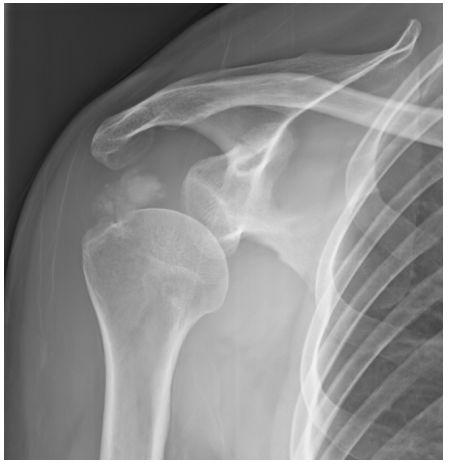

73.59歲女性病人意外跌倒後,主訴左肩疼痛,X光檢查如圖,最可能之診斷為何?(A)calcified tendinosis (B)avulsion fracture of greater tuberosity (C)bone metastasis (D)primary osteoblastic bone tumor (E)一律給分